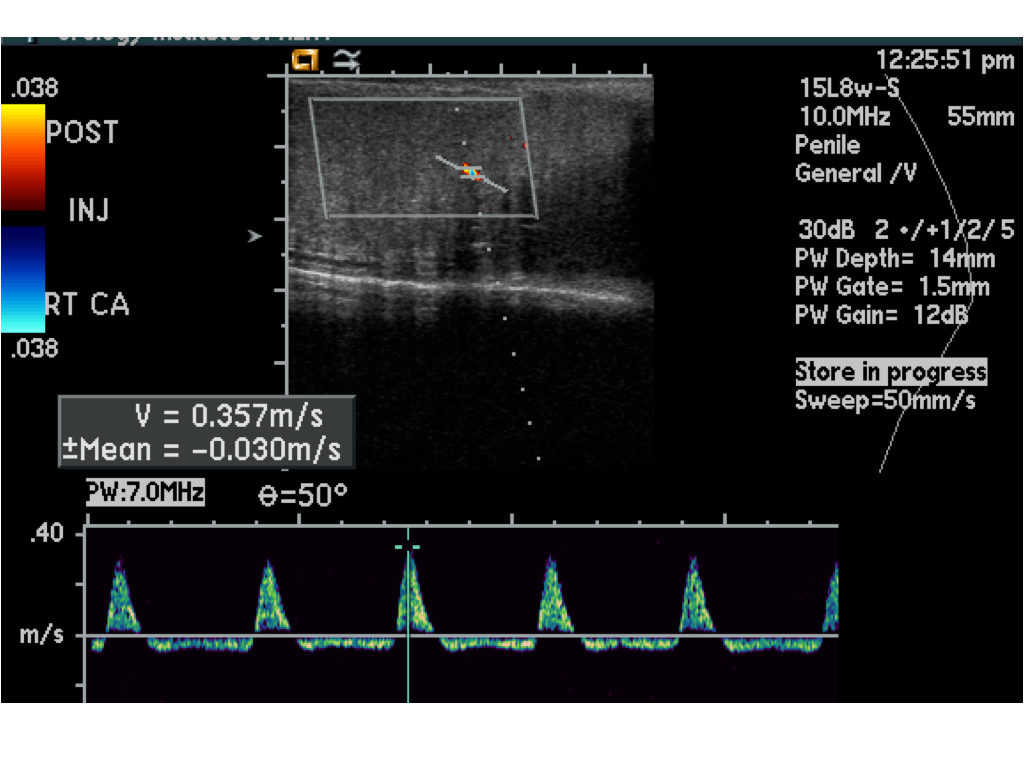

A disfunção erétil (DE) afeta muitos homens e pode ter diversas causas, desde fatores psicológicos até problemas vasculares. Para um diagnóstico preciso, um dos exames mais eficazes é o ultrassom Doppler Peniano com fármaco indução, que avalia o fluxo sanguíneo no pênis e a resposta vascular à ereção. Além disso, em alguns casos, o tratamento com injeções intracavernosas pode ser uma solução eficaz para restaurar a função erétil.

Esse exame é um método invasivo que analisa a circulação sanguínea nos corpos cavernosos do pênis. Ele é feito em duas etapas:

1. Medição inicial do fluxo sanguíneo – o pênis é avaliado em estado de repouso para verificar a circulação basal.

2. Indução farmacológica da ereção – um medicamento vasodilatador (como a prostaglandina E1 ou um conjunto de medicações) é injetado no corpo cavernoso para estimular a ereção, permitindo a análise do fluxo arterial e do retorno venoso.